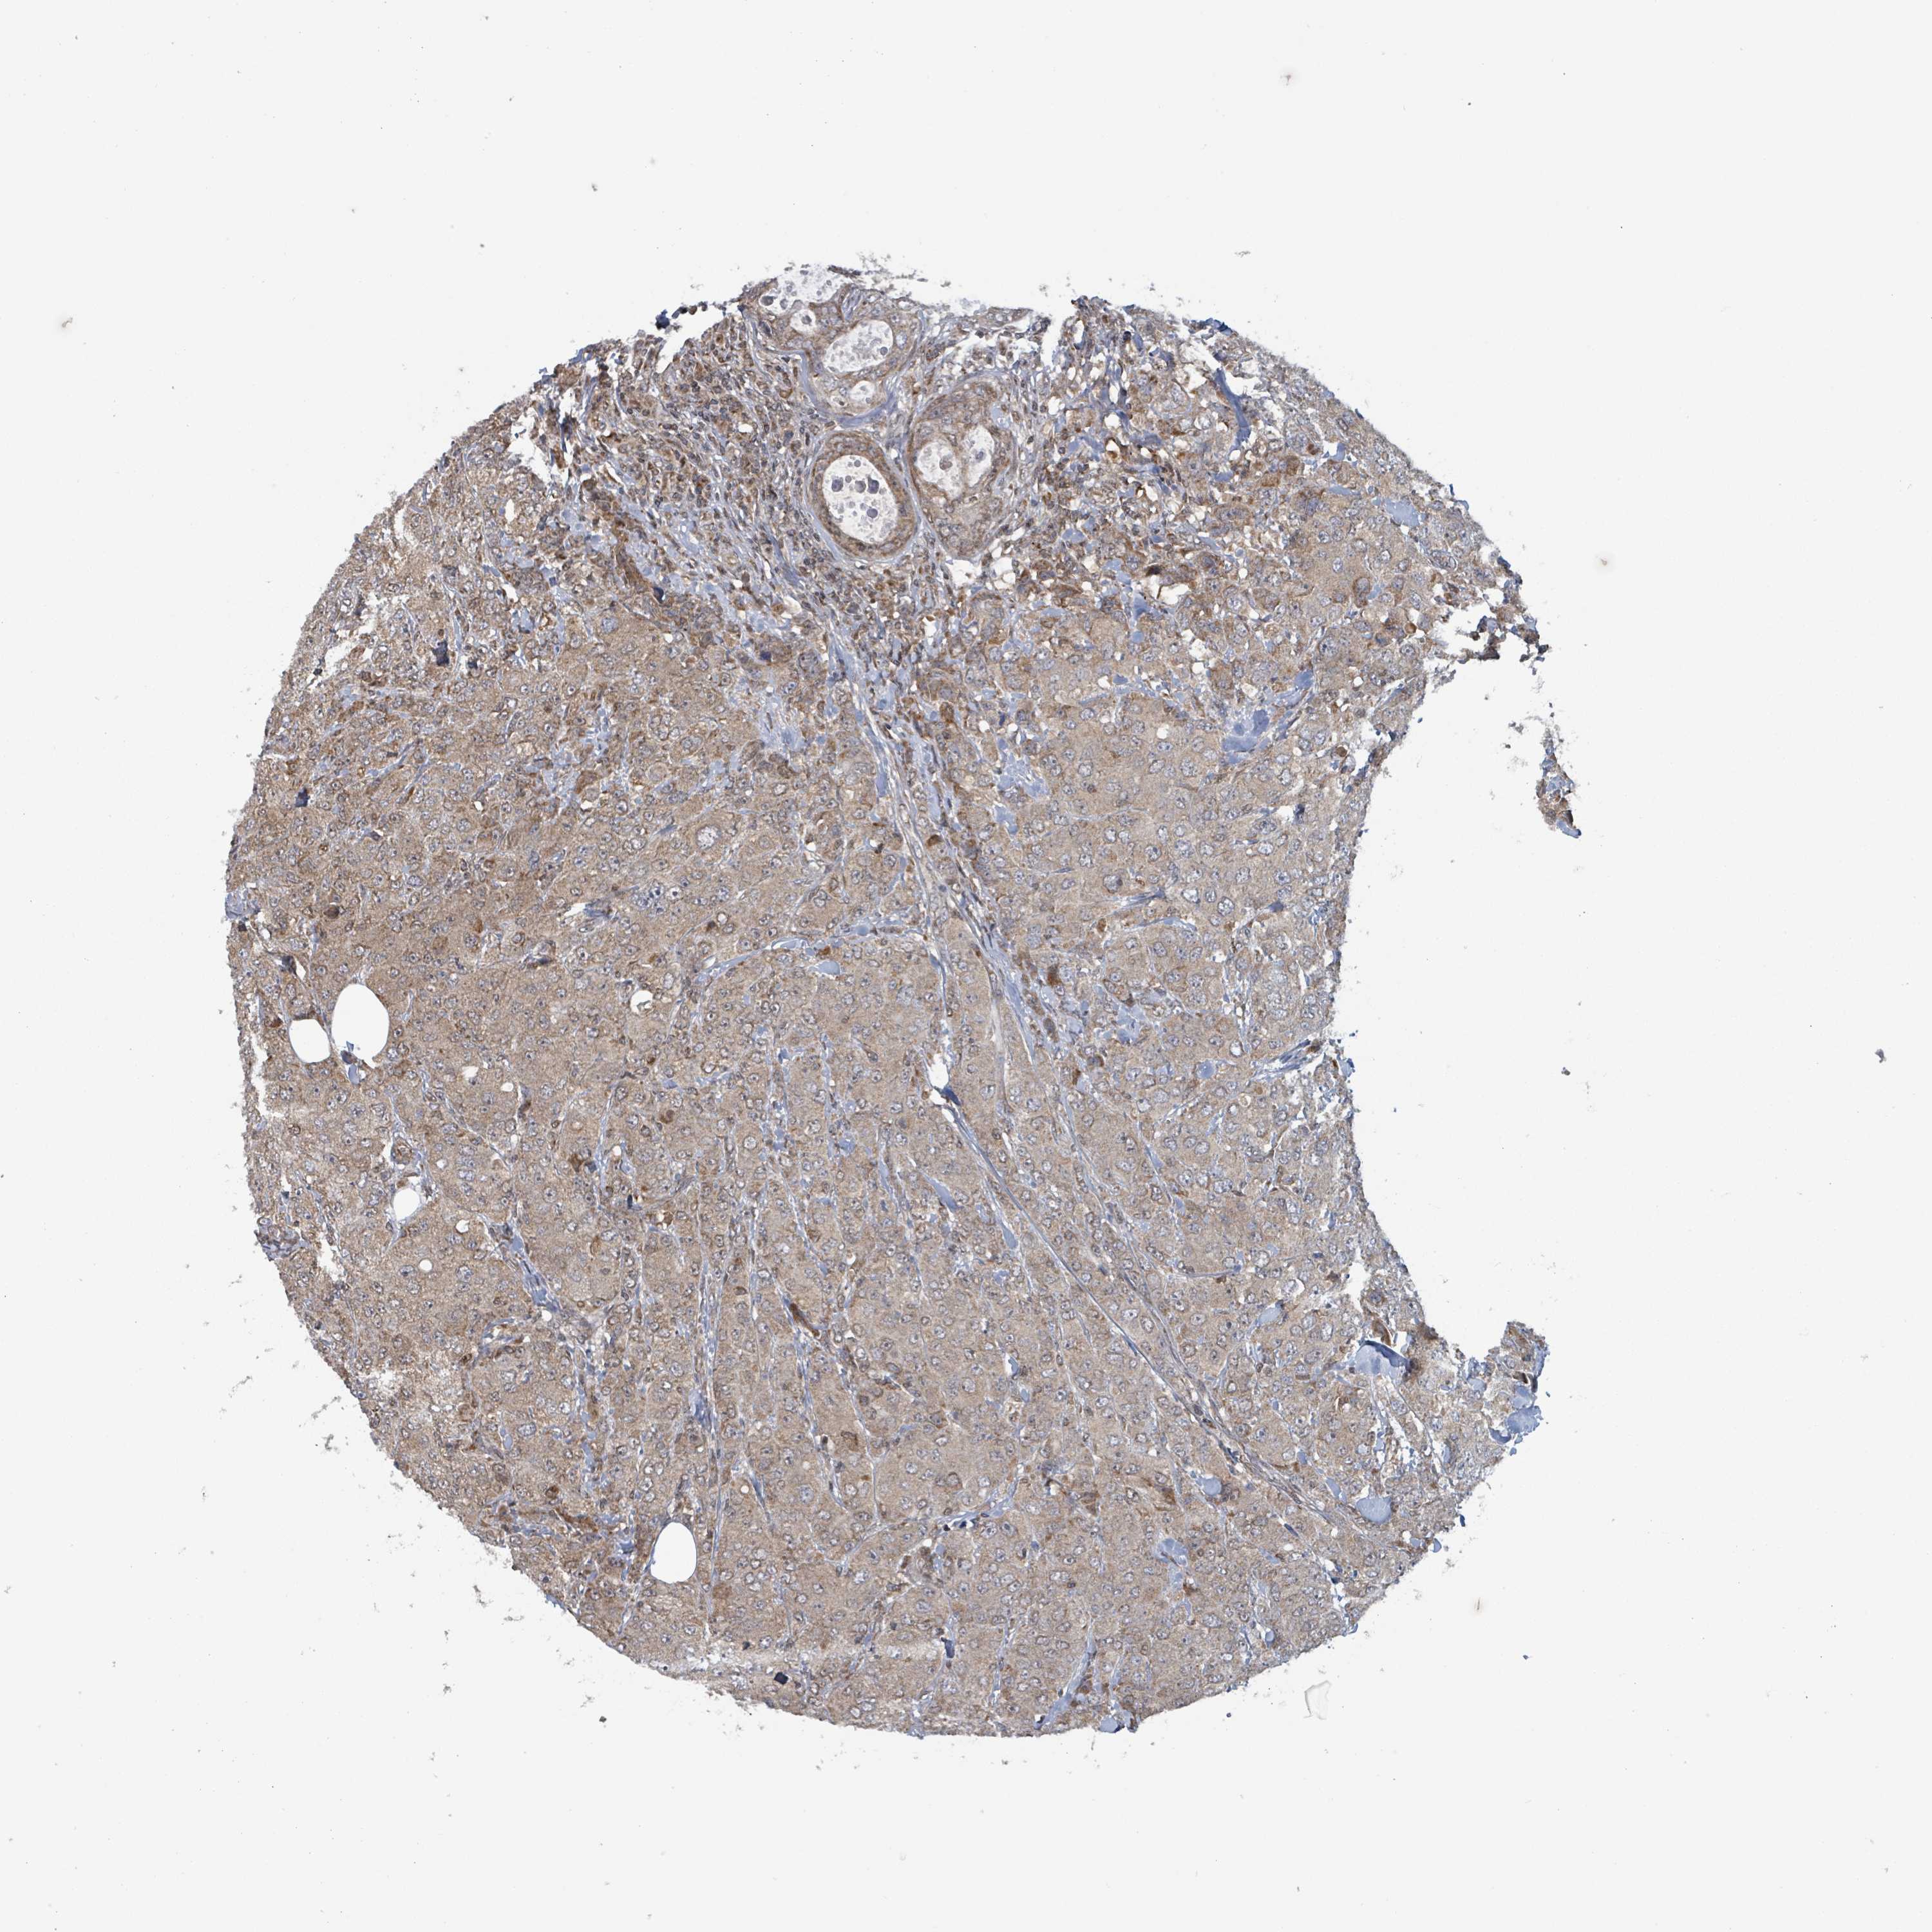

BRCA TCGA BRCA VALIDATION PROTEIN EXPRESSION